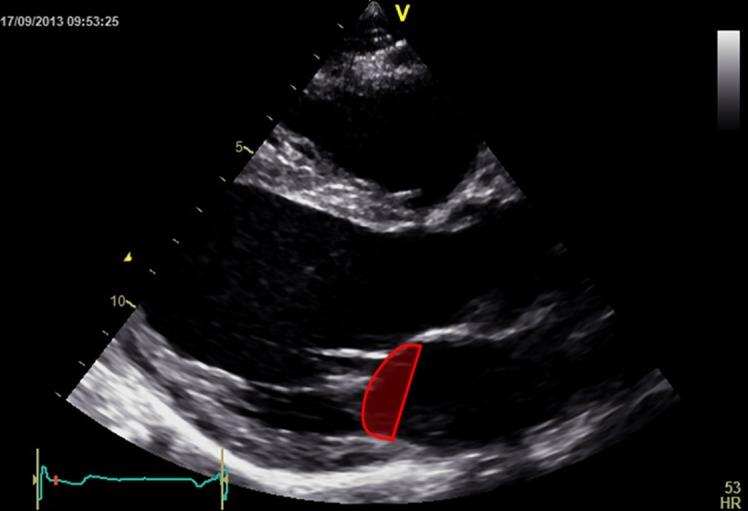

Quantitative analysis is an important part of the morphological assessment of the diseased mitral valve. It can be used to describe valve anatomy, pathology, function and the mechanisms of disease. Echocardiography is the main source of indirect quantitative data that is comparable with direct anatomic or surgical measurements. Furthermore, it can relate morphology with function. This review provides an account of current mitral valve quantification techniques and clinical applications.